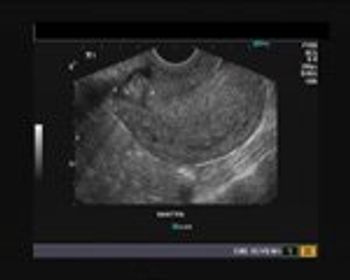

This is a case of a female patient presenting with a history of 5 weeks of amenorrhoea and scanty bleeding. She was sent for diagnostic ultrasound imaging.

Our patient presents with a history of 5 weeks of amenorrhoea and scanty bleeding per vagina. Based on her history and ultrasound images, what is your diagnosis?